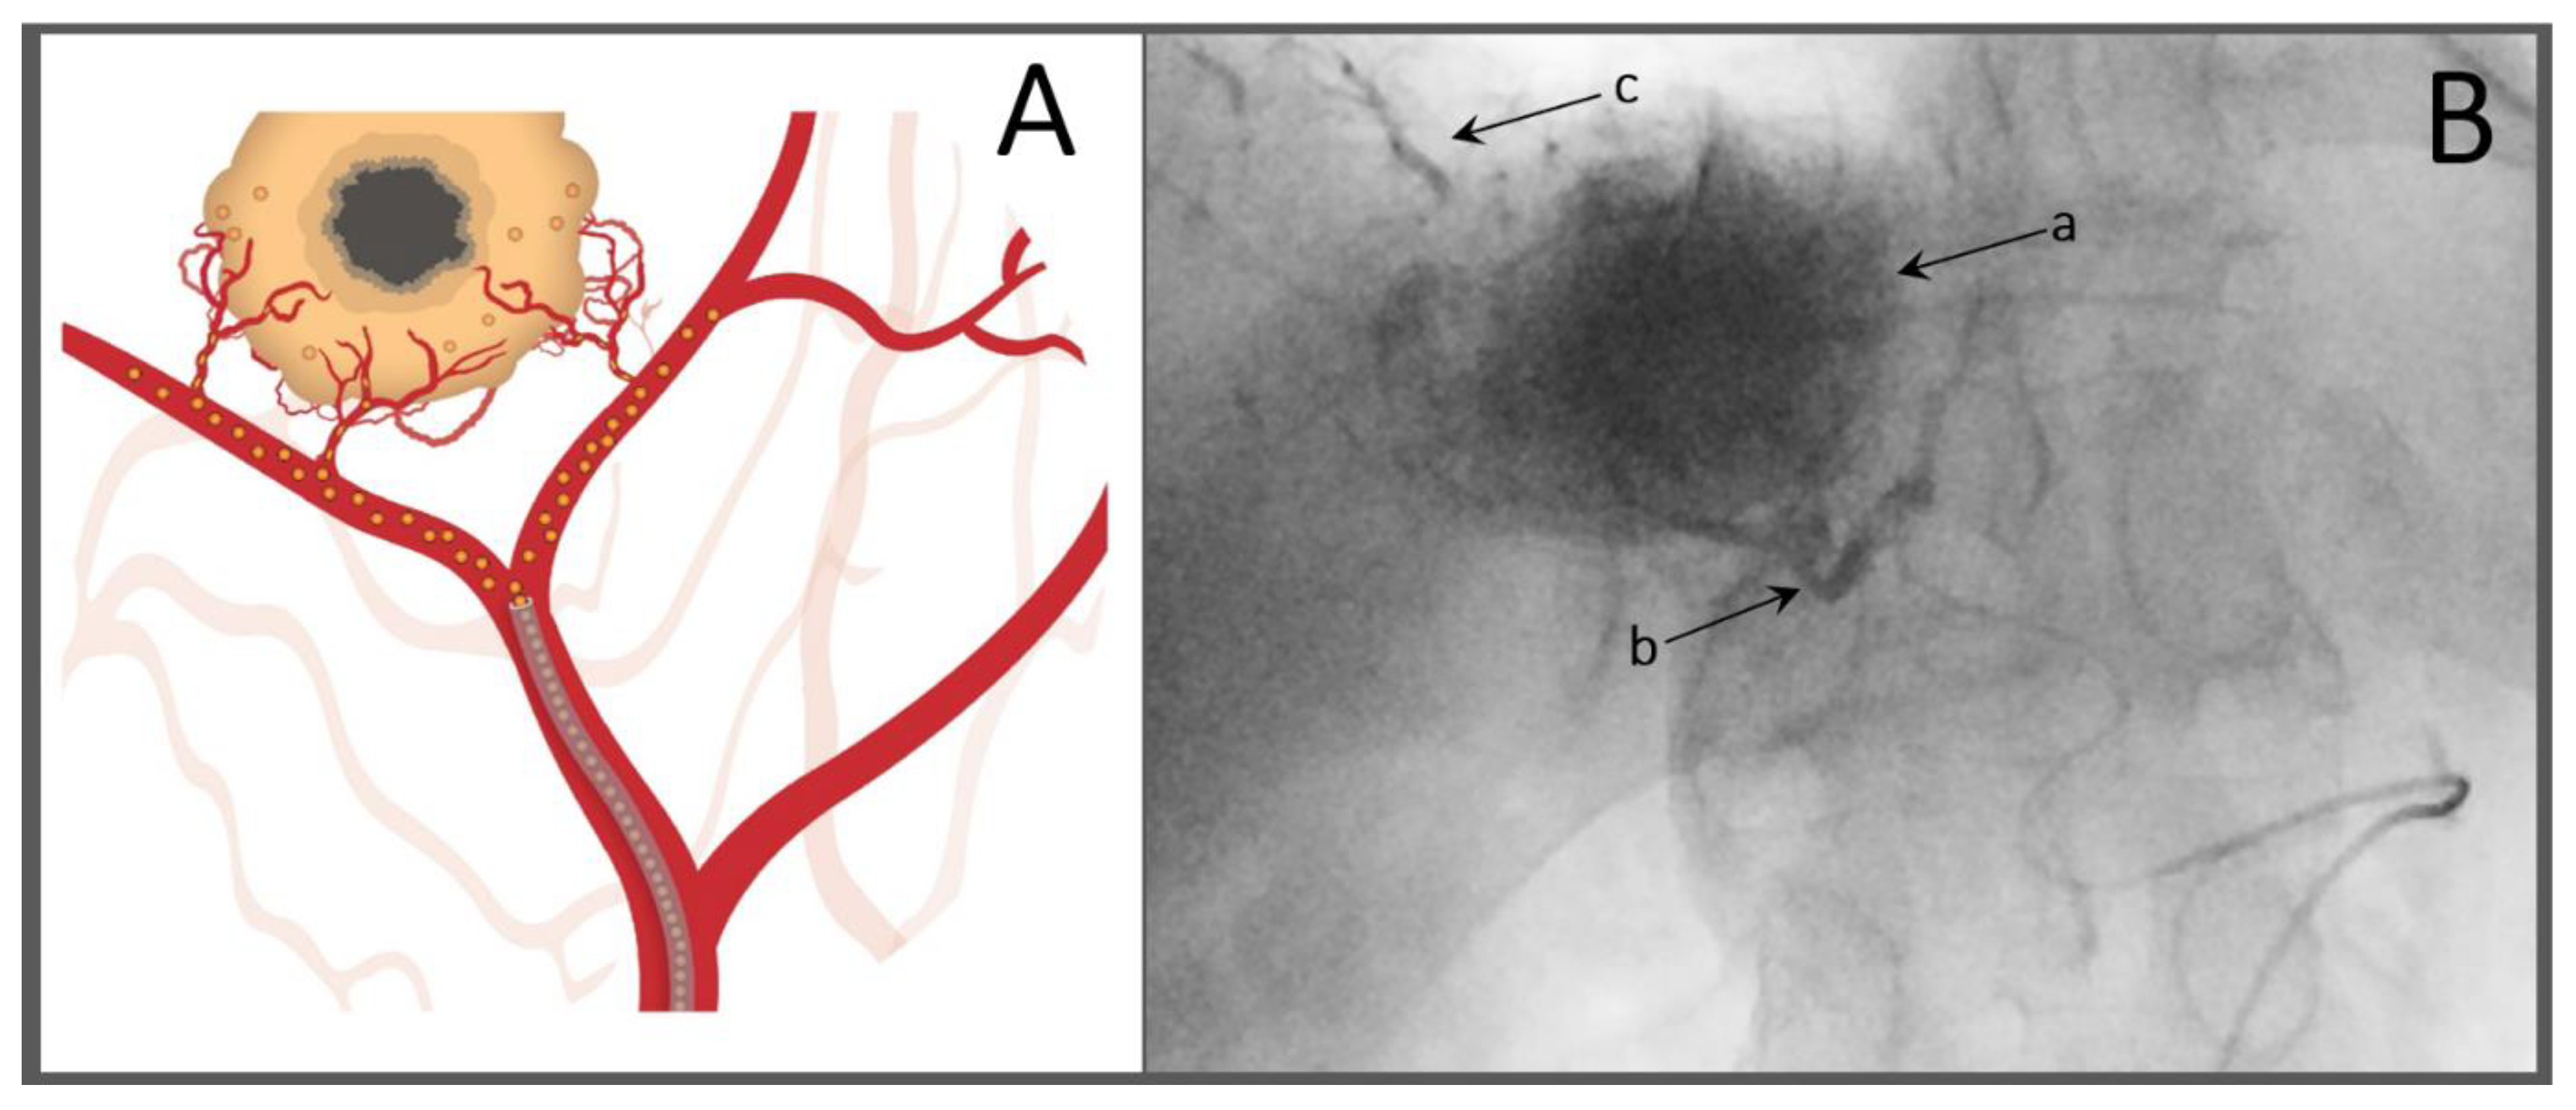

- Miyayama, S.; Matsui, O.; Yamashiro, M.; Ryu, Y.; Kaito, K.; Ozaki, K.; Takeda, T.; Yoneda, N.; Notsumata, K.; Toya, D.; et al. Ultraselective transcatheter arterial chemoembolization with a 2-f tip microcatheter for small hepatocellular carcinomas: Relationship between local tumor recurrence and visualization of the portal vein with iodized oil. J. Vasc. Interv. Radiol. 2007, 18, 365–376. [Google Scholar] [CrossRef]

- Miyayama, S.; Mitsui, T.; Zen, Y.; Sudo, Y.; Yamashiro, M.; Okuda, M.; Yoshie, Y.; Sanada, T.; Notsumata, K.; Tanaka, N.; et al. Histopathological findings after ultraselective transcatheter arterial chemoembolization for hepatocellular carcinoma. Hepatol. Res. 2009, 39, 374–381. [Google Scholar] [CrossRef]

- Bannangkoon, K.; Hongsakul, K.; Tubtawee, T.; Piratvisuth, T. Safety margin of embolized area can reduce local recurrence of hepatocellular carcinoma after superselective transarterial chemoembolization. Clin. Mol. Hepatol. 2019, 25, 74–85. [Google Scholar] [CrossRef]